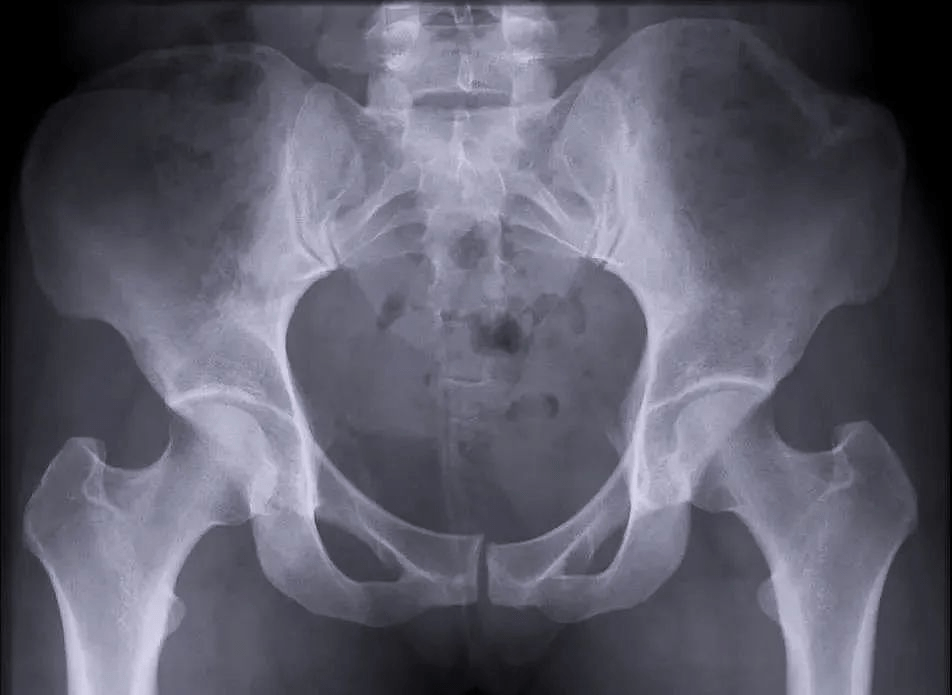

We usually divide pelvic fractures into traumatic fractures (that is, violent fractures) and pathological fractures. Violent fractures are mostly caused by trauma. Pathological fractures may be caused by patients suffering from certain diseases, such as tumors, osteoporosis, and other fractures that occur when external forces are small. This is called "pathological fractures".

2、 Stable fracture & unstable fracture

In addition, according to whether the pelvic fracture is stable or not, it can be divided into stable fracture and unstable fracture. If it is an unstable fracture, the doctor may recommend that the patient undergo surgery to turn the unstable fracture into a stable fracture.

The PLX119C is a large flat panel C-arm with a 30cm x 30cm flat panel detector and a large field of view, which can present more image details and has advantages for applications such as bilateral pelvic fracture type surgery or posterior pelvic ring internal fixation.

One exposure can obtain images of all fracture parts, simplify the exposure process and improve the operation efficiency.